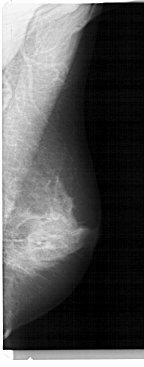

A_1929_1.RIGHT_MLO

RIGHT_MLO LINES 5491 PIXELS_PER_LINE 2146 BITS_PER_PIXEL 12 RESOLUTION 43.5 NON_OVERLAY